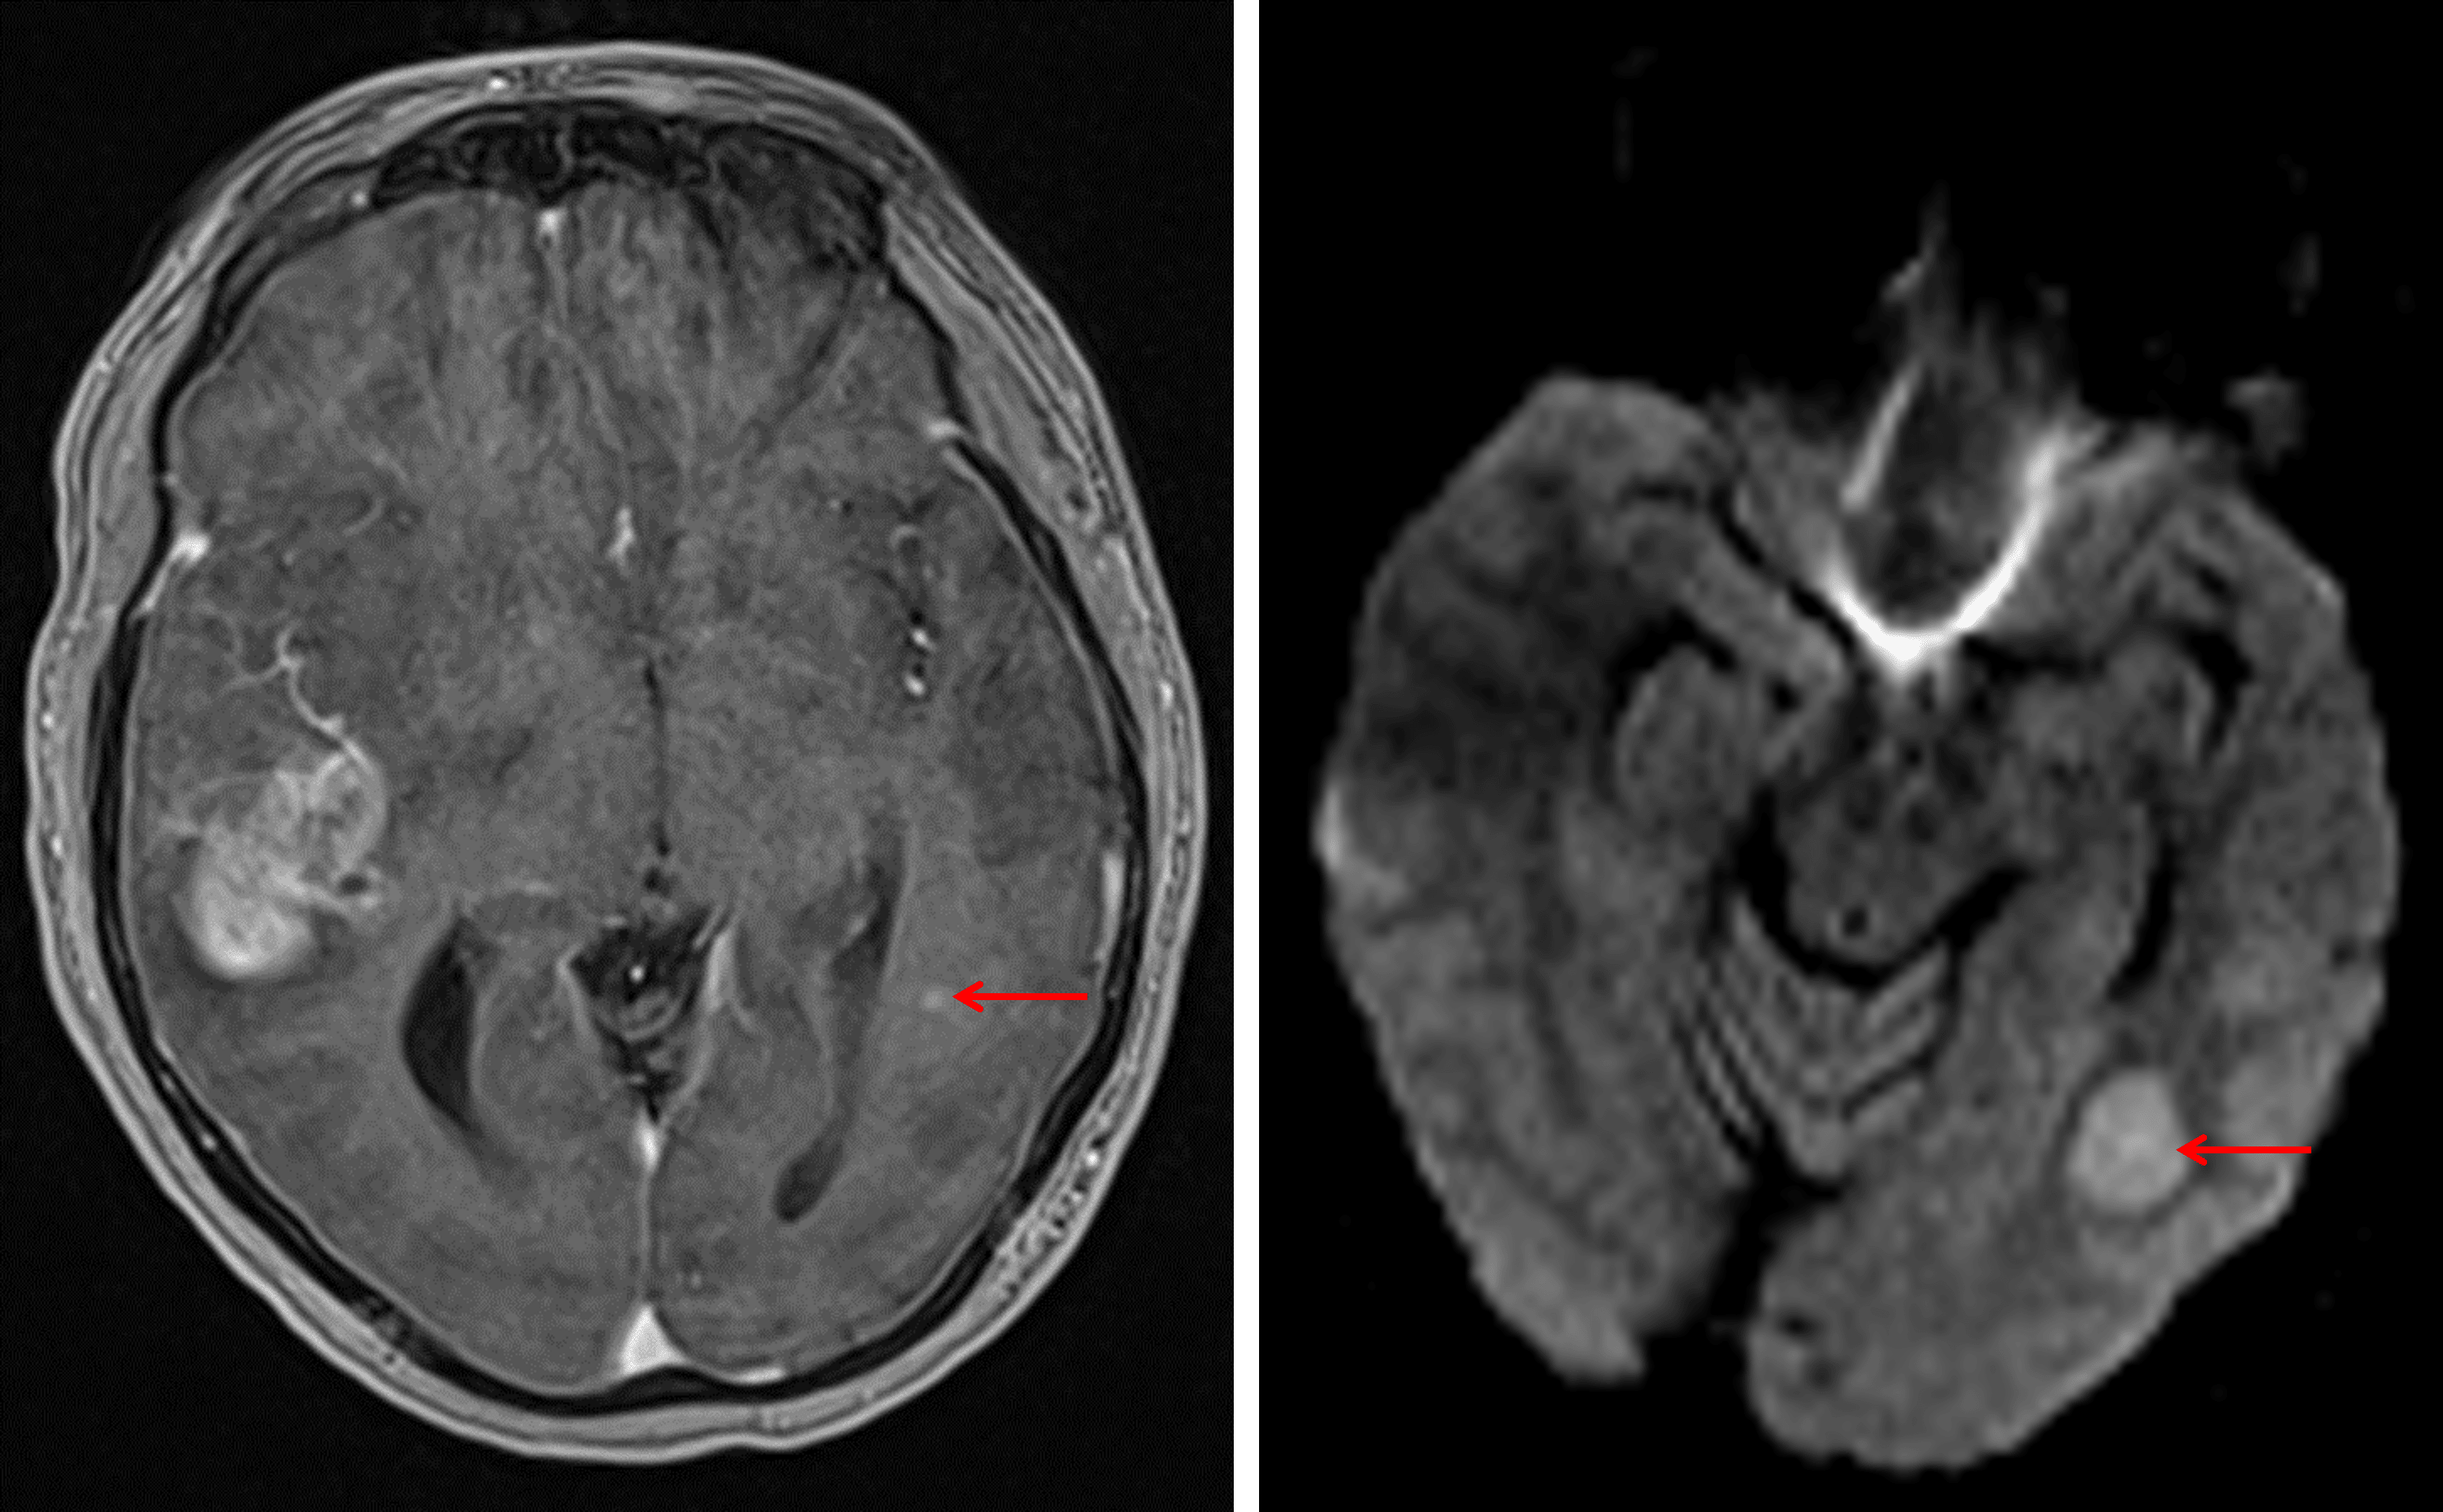

- Additionally masslike area of restricted diffusion in the posterior left temporal lobe with a corresponding focus of enhancement along its anterior margin

Additional masslike area of restricted diffusion in the posterior left temporal lobe with a nodular focus of enhancement along its anterior margin (red arrows).